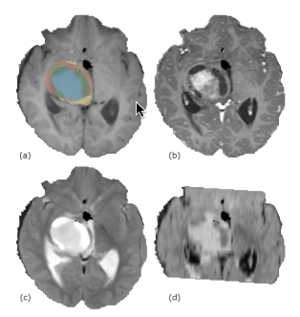

A Novel Tool for Supervised Segmentation Using 3D Slicer

Publication: Symmetry 2018 Nov 12; 10:627. | PDF Authors: Daniel Chalupa, Jan Mikulka. Institution: Department of Theoretical and Experimental Electrical Engineering, Brno University of Technology, Brno, Czech Republic. Abstract: The rather impressive extension library of medical image-processing platform 3D Slicer lacks a wide range of machine-learning toolboxes. The authors have developed such a toolbox that incorporates commonly used machine-learning libraries. The extension uses a simple graphical user interface that allows the user to preprocess data, train a classifier, and use that classifier in common medical image-classification tasks, such as tumor staging or various anatomical segmentations without a deeper knowledge of the inner workings of the classifiers. A series of experiments were carried out to showcase the capabilities of the extension and quantify the symmetry between the physical characteristics of pathological tissues and the parameters of a classifying model. These experiments also include an analysis of the impact of training vector size and feature selection on the sensitivity and specificity of all included classifiers. The results indicate that training vector size can be minimized for all classifiers. Using the data from the Brain Tumor Segmentation Challenge, Random Forest appears to have the widest range of parameters that produce sufficiently accurate segmentations, while optimal Support Vector Machines’ training parameters are concentrated in a narrow feature space.. Funding:

|